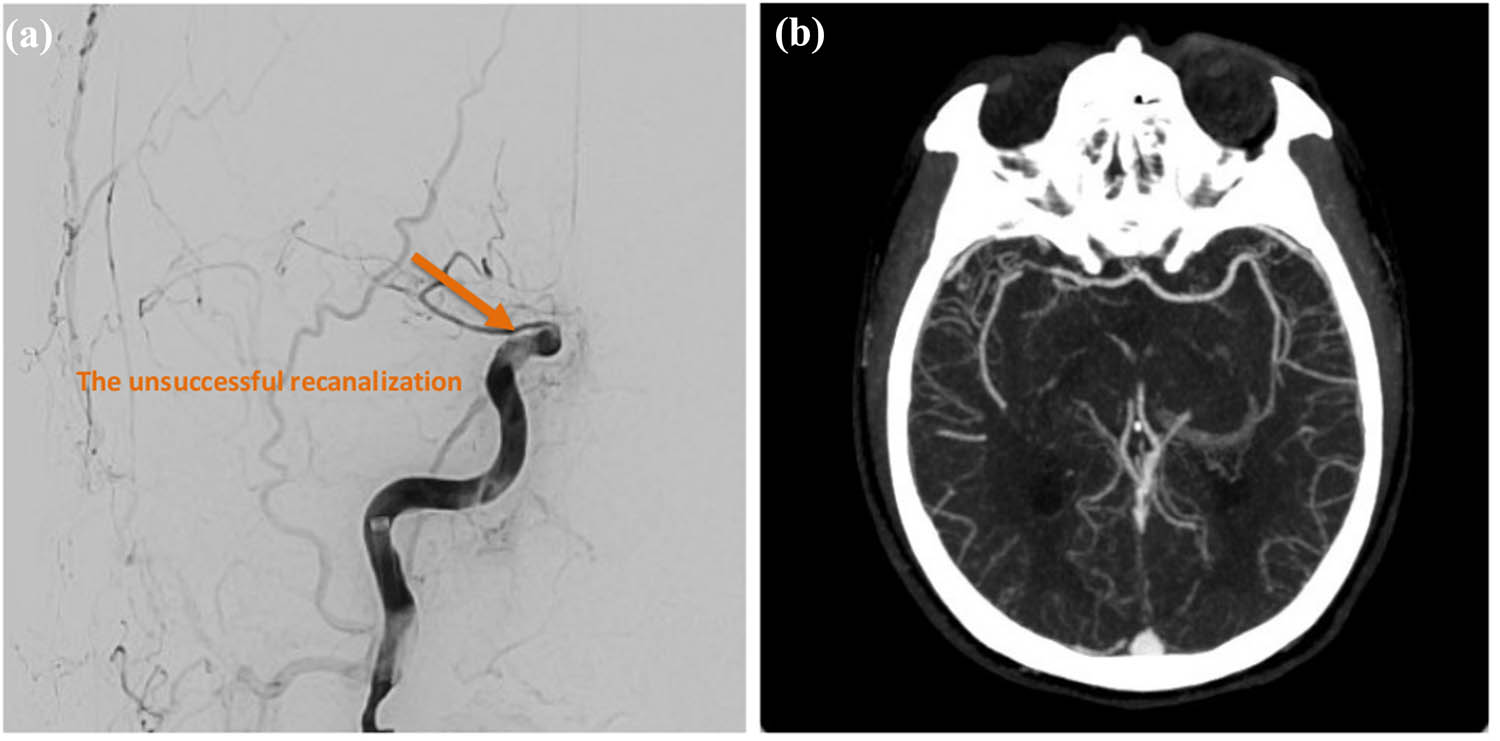

Intravenous thrombolysis with recombinant tissue plasminogen activator (rt-PA) was contraindicated due to ongoing anticoagulant therapy with apixaban (ELIQUIS) and a delayed presentation beyond the 4.5-h therapeutic window. The patient subsequently underwent emergency endovascular thrombectomy. The procedure involved two aspiration attempts, followed by three additional attempts using a stent retriever. Despite these interventions, successful recanalization was not achieved, with a final modified Thrombolysis in Cerebral Infarction (mTICI) score of 0. On November 13, 2024, brain magnetic resonance imaging (MRI) demonstrated acute infarcts involving the posterior limb of the right internal capsule, caudate head, hippocampus, and occipital lobe, along with additional embolic infarctions in the right frontal and parietal lobes. Magnetic resonance angiography (MRA) confirmed occlusion of the right ICA at the cavernous segment, as well as occlusion of the right fetal-type posterior cerebral artery (Figure 2).

Endovascular thrombectomy findings. (a) Digital subtraction angiography reveals acute occlusion of the distal segment of the right ICA. (b) Post-procedural angiography demonstrates unsuccessful recanalization, with a mTICI score of 0, indicating persistent occlusion. Infarction involving the basal ganglia is also noted. Orange arrow: The orange arrow denotes an area of unsuccessful recanalization.